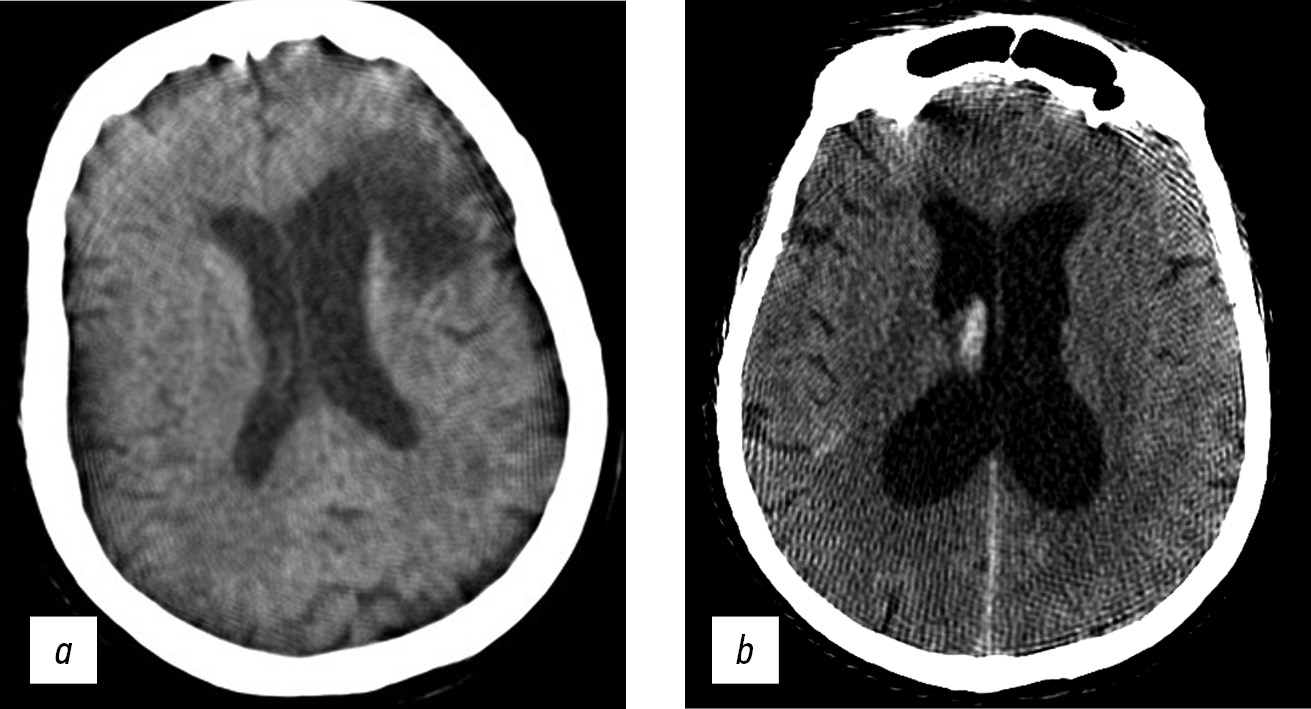

Brain CT was used to diagnose acute cerebrovascular accident, intracranial hematomas, brain tumors, and traumatic skull injuries (Fig. 7).

Fig. 7. Axial computed tomographic images of the brain: (a) reconstruction of a 3-mm low-density area at the anterior horn of the left lateral ventricle, in the periventricular, subcortical direction (CT image of subacute cerebrovascular accident of the left middle cerebral artery), and (b) a 1-mm site of subarachnoid hemorrhage with blood breakthrough into the ventricular system (vicarious hydrocephalus).

Windmill artifacts (Fig. 8a) were mixed with strike artifacts and helical scanning [5], and artifacts intensified at the level of skull base, where significant beam hardening and scattering artifacts occurred (Fig. 8, b). Therefore, subtentorial brain areas were challenging to assess.

Fig. 8. Axial (a) and sagittal (b) computed tomographic images of the head in the region of the posterior cranial fossa and base of skull showed windmill, strike, beam hardening, and scattering artifacts. Area of bone structures and the posterior fossa is hard to evaluate.